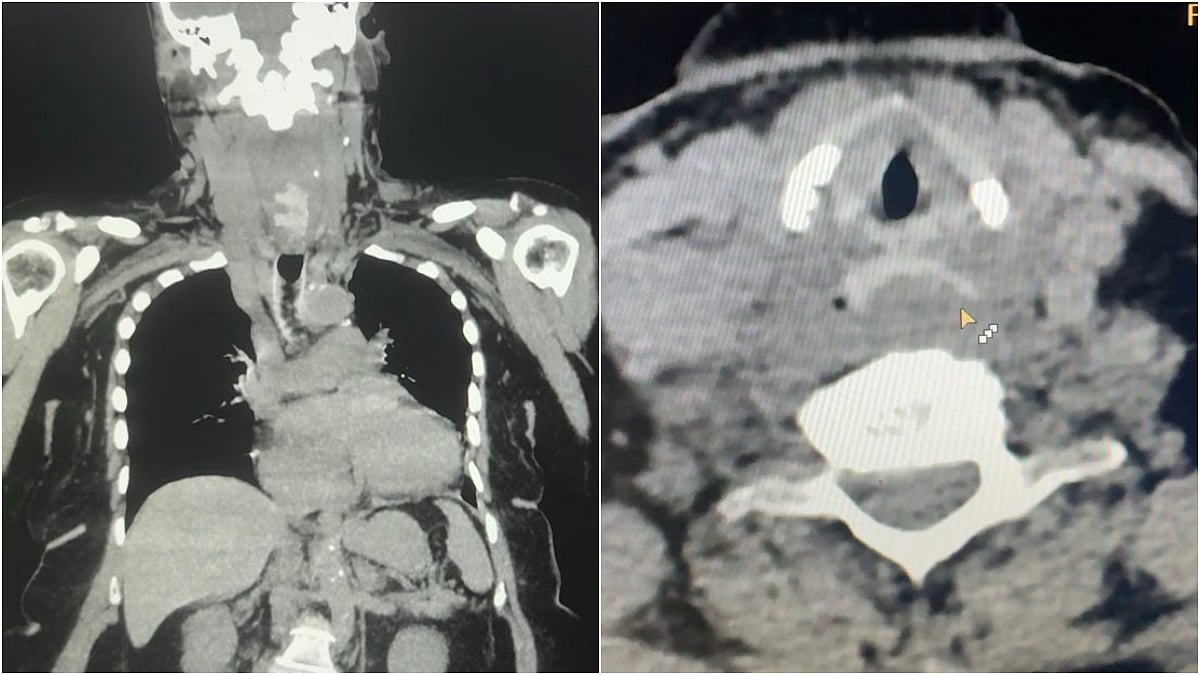

A gastrointestinal (GI) endoscopy revealed the denture was stuck just below the upper esophageal sphincter (UES). Attempts to retrieve it using endoscopic instruments, including rat-tooth forceps, were unsuccessful due to deep embedding in the esophageal mucosa—making surgical intervention the only viable option.